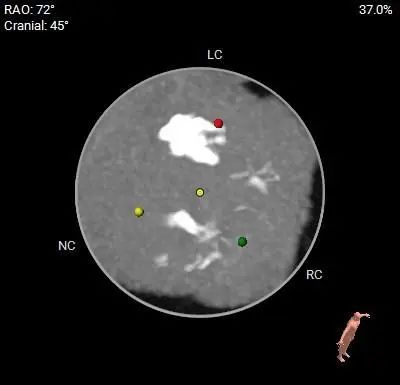

术前CT评估

主动脉根部测量

31mm超大瓣环,敞口流出道,瓣膜锚定难度高;结合多平面分析,推荐瓣环上3-4mm开始定位释放。

窦部及STJ内径尚可,升主动脉扩张。

左室内径偏大,EF值36%,心尖部较薄,术中密切关注血流动力学变化,注意加硬导丝位置,避免心室穿孔

左右冠脉高度尚可,冠脉阻挡风险相对较低

轻中度钙化,一定程度上辅助可瓣膜锚定